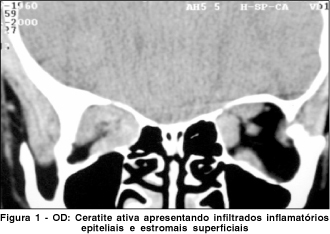

Paciente do sexo feminino com 34 anos, usuária de lente de contato gelatinosa há três anos em ambos os olhos. Referia intensa dor ocular no olho esquerdo há duas semanas acompanhada por fotofobia, hiperemia conjuntival, sensação de corpo estranho e turvação visual. A acuidade visual com correção era de 20/20 no olho direito e 20/200 no esquerdo. Observou-se ao exame biomicroscópico do olho esquerdo, córnea com infiltrado estromal, aspecto granular, cor branco-acinzentada, edema epitelial de moderada intensidade e erosões ponteadas, localizadas na região paracentral enquanto que o outro olho se apresentava normal. Devido a suspeita diagnóstica de ceratite por Acanthamoeba, foi realizado a colheita do material da lesão corneana. A análise laboratorial não identificou o agente etiológico em coloração de lâminas por Gram e Giemsa, porém após 20 dias mostrou crescimento da Acanthamoeba em meio de Agar não nutriente com E. coli. Com a suspeita biomicroscópica para ceratite por Acanthamoeba mesmo com o resultado das lâminas negativo, foi optado pelo tratamento do agente com: polihexametilbiguanida 0,02% tópica de 1/1 h, isethionato de propamidine (Brolene®) tópico de 1/1 h, neomicina tópica de 2/2 h e cetoconazole 200 mg de 12/12 h. No 30º dia de evolução queixou-se no olho direito, de embaçamento visual e olho levemente vermelho, a melhor acuidade visual era 20/100, notando-se ao exame biomicroscópico, em sua região central, a presença de infiltrados epiteliais e estromal superficial, córnea corando em ponteados, à fluoresceína (Figura 1). Realizado colheita laboratorial com resultados semelhante ao olho esquerdo. Foi também iniciado o tratamento tópico idêntico ao utilizado no outro olho.